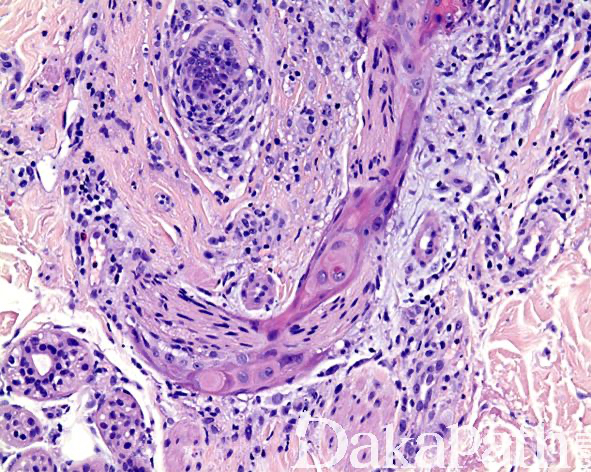

镜下见病变位于真皮浅层,由多个增生的神经束组成,神经束周围可见由鳞状上皮所组成的鞘样结构围绕,神经束内可见轴突、施万细胞和神经束膜细胞;

上皮鞘常与表面上皮相延续,细胞形态温和,可见散在的角化不良的细胞,无核异型性和核分裂象,可能来自于毛囊特别是漏斗部上皮;

上皮鞘周围间质内可见疏松的纤维化和多少不等的淋巴细胞浸润。